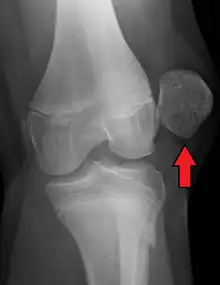

![]() | |

| X-ray showing a patellar dislocation, with the patella out to the side. | |

A patellar dislocation typically occurs when the knee is straight and the lower leg is bent outwards when twisting.[1][2] Occasionally, it occurs when the knee is bent and the patella is struck directly.[1] Commonly associated sports include soccer, gymnastics, and ice hockey.[2] Dislocations nearly always occur away from the midline.[2] Diagnosis is typically based on symptoms and supported by X-rays.[2]